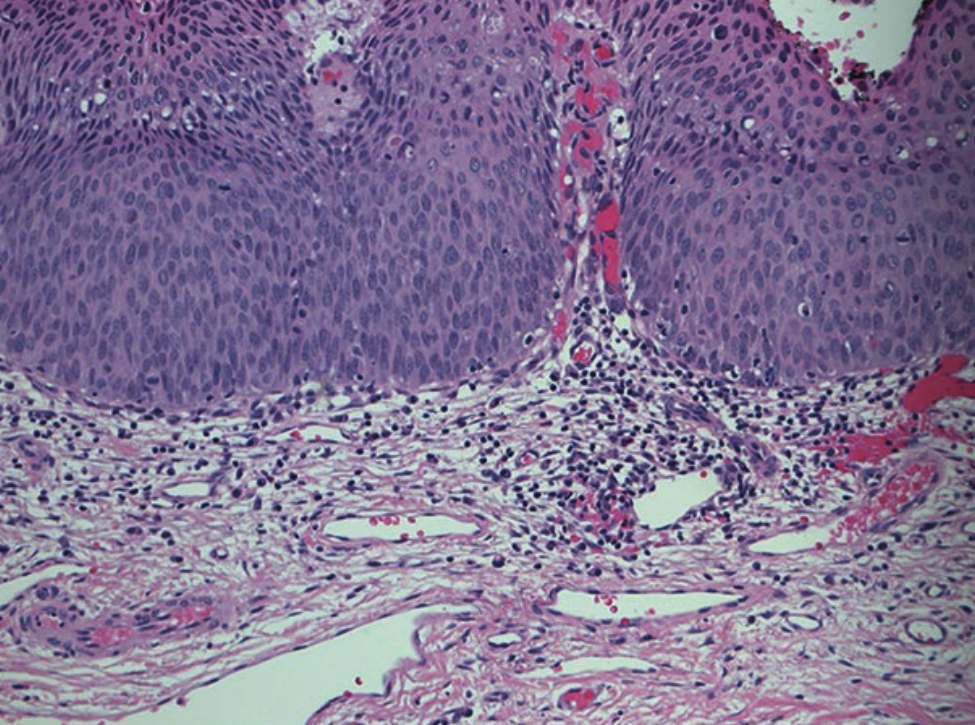

宫颈癌和HGSIL/CIN2/CIN3的发展都与HPV基因组整合到宿主基因组中以及随后两个HPV早期基因产物E6和E7的表达有关,这两个基因产物分别使p53和pRb失活。病毒整合位点虽然随机分布在人类基因组内,但主要发生在人类DNA容易断裂的位点(例如,脆弱位点),并且似乎只影响HPV基因组本身的表达。具体地说,E1和E2在整合过程中最常被破坏,而E6和E7病毒癌基因被保留,导致结构性表达。E6和E7的表达在功能上是启动和维持肿瘤转化所必需的。在形态学上,在细胞水平上,高度上皮内病变的特点是核浆比高。而在组织学上,高度恶性病变表现为全厚度,细胞不成熟,有丝分裂活跃(Fig. 15.4)。

Fig 15.4 放大20倍CIN-2/CIN3组织苏木精-伊红染色